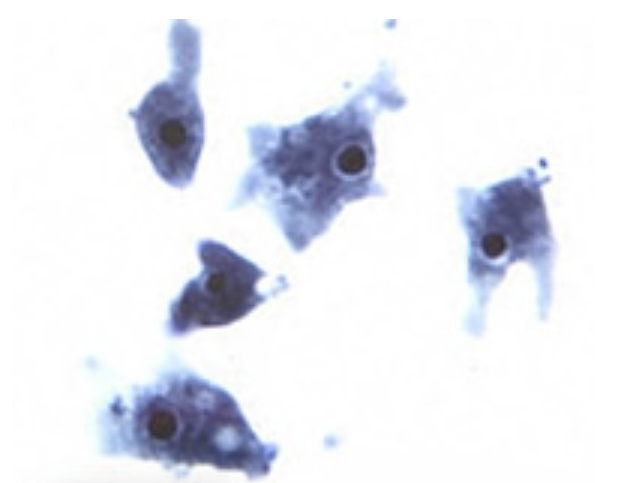

Неглерия Фоулера - фото из Википедии